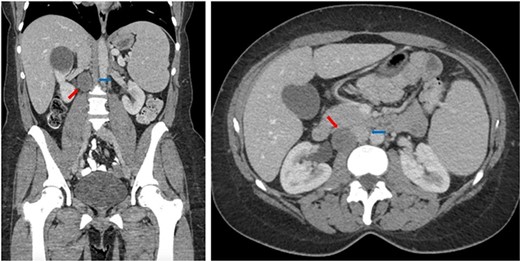

The patient was taken to the operating room and after adequate general anesthesia was induced, pneumoperitoneum was established. Four 8-mm robotic trocars (periumbilical, left upper quadrant, right upper quadrant mid-clavicular line, and right upper quadrant anterior axillary line) and two assistant trocars (12-mm left lower quadrant and 5-mm right lower quadrant) were placed. The daVinci Xi platform was utilized. Cattel-Braasch and Kocher maneuvers were performed to mobilize the right colon and duodenum medially, respectively, in order to expose the IVC and the retrocaval Schwannoma (see Fig. 2).

Intraoperative images showing the retrocaval schwannoma (red arrow), IVC (blue arrow), and duodenum (green arrow).